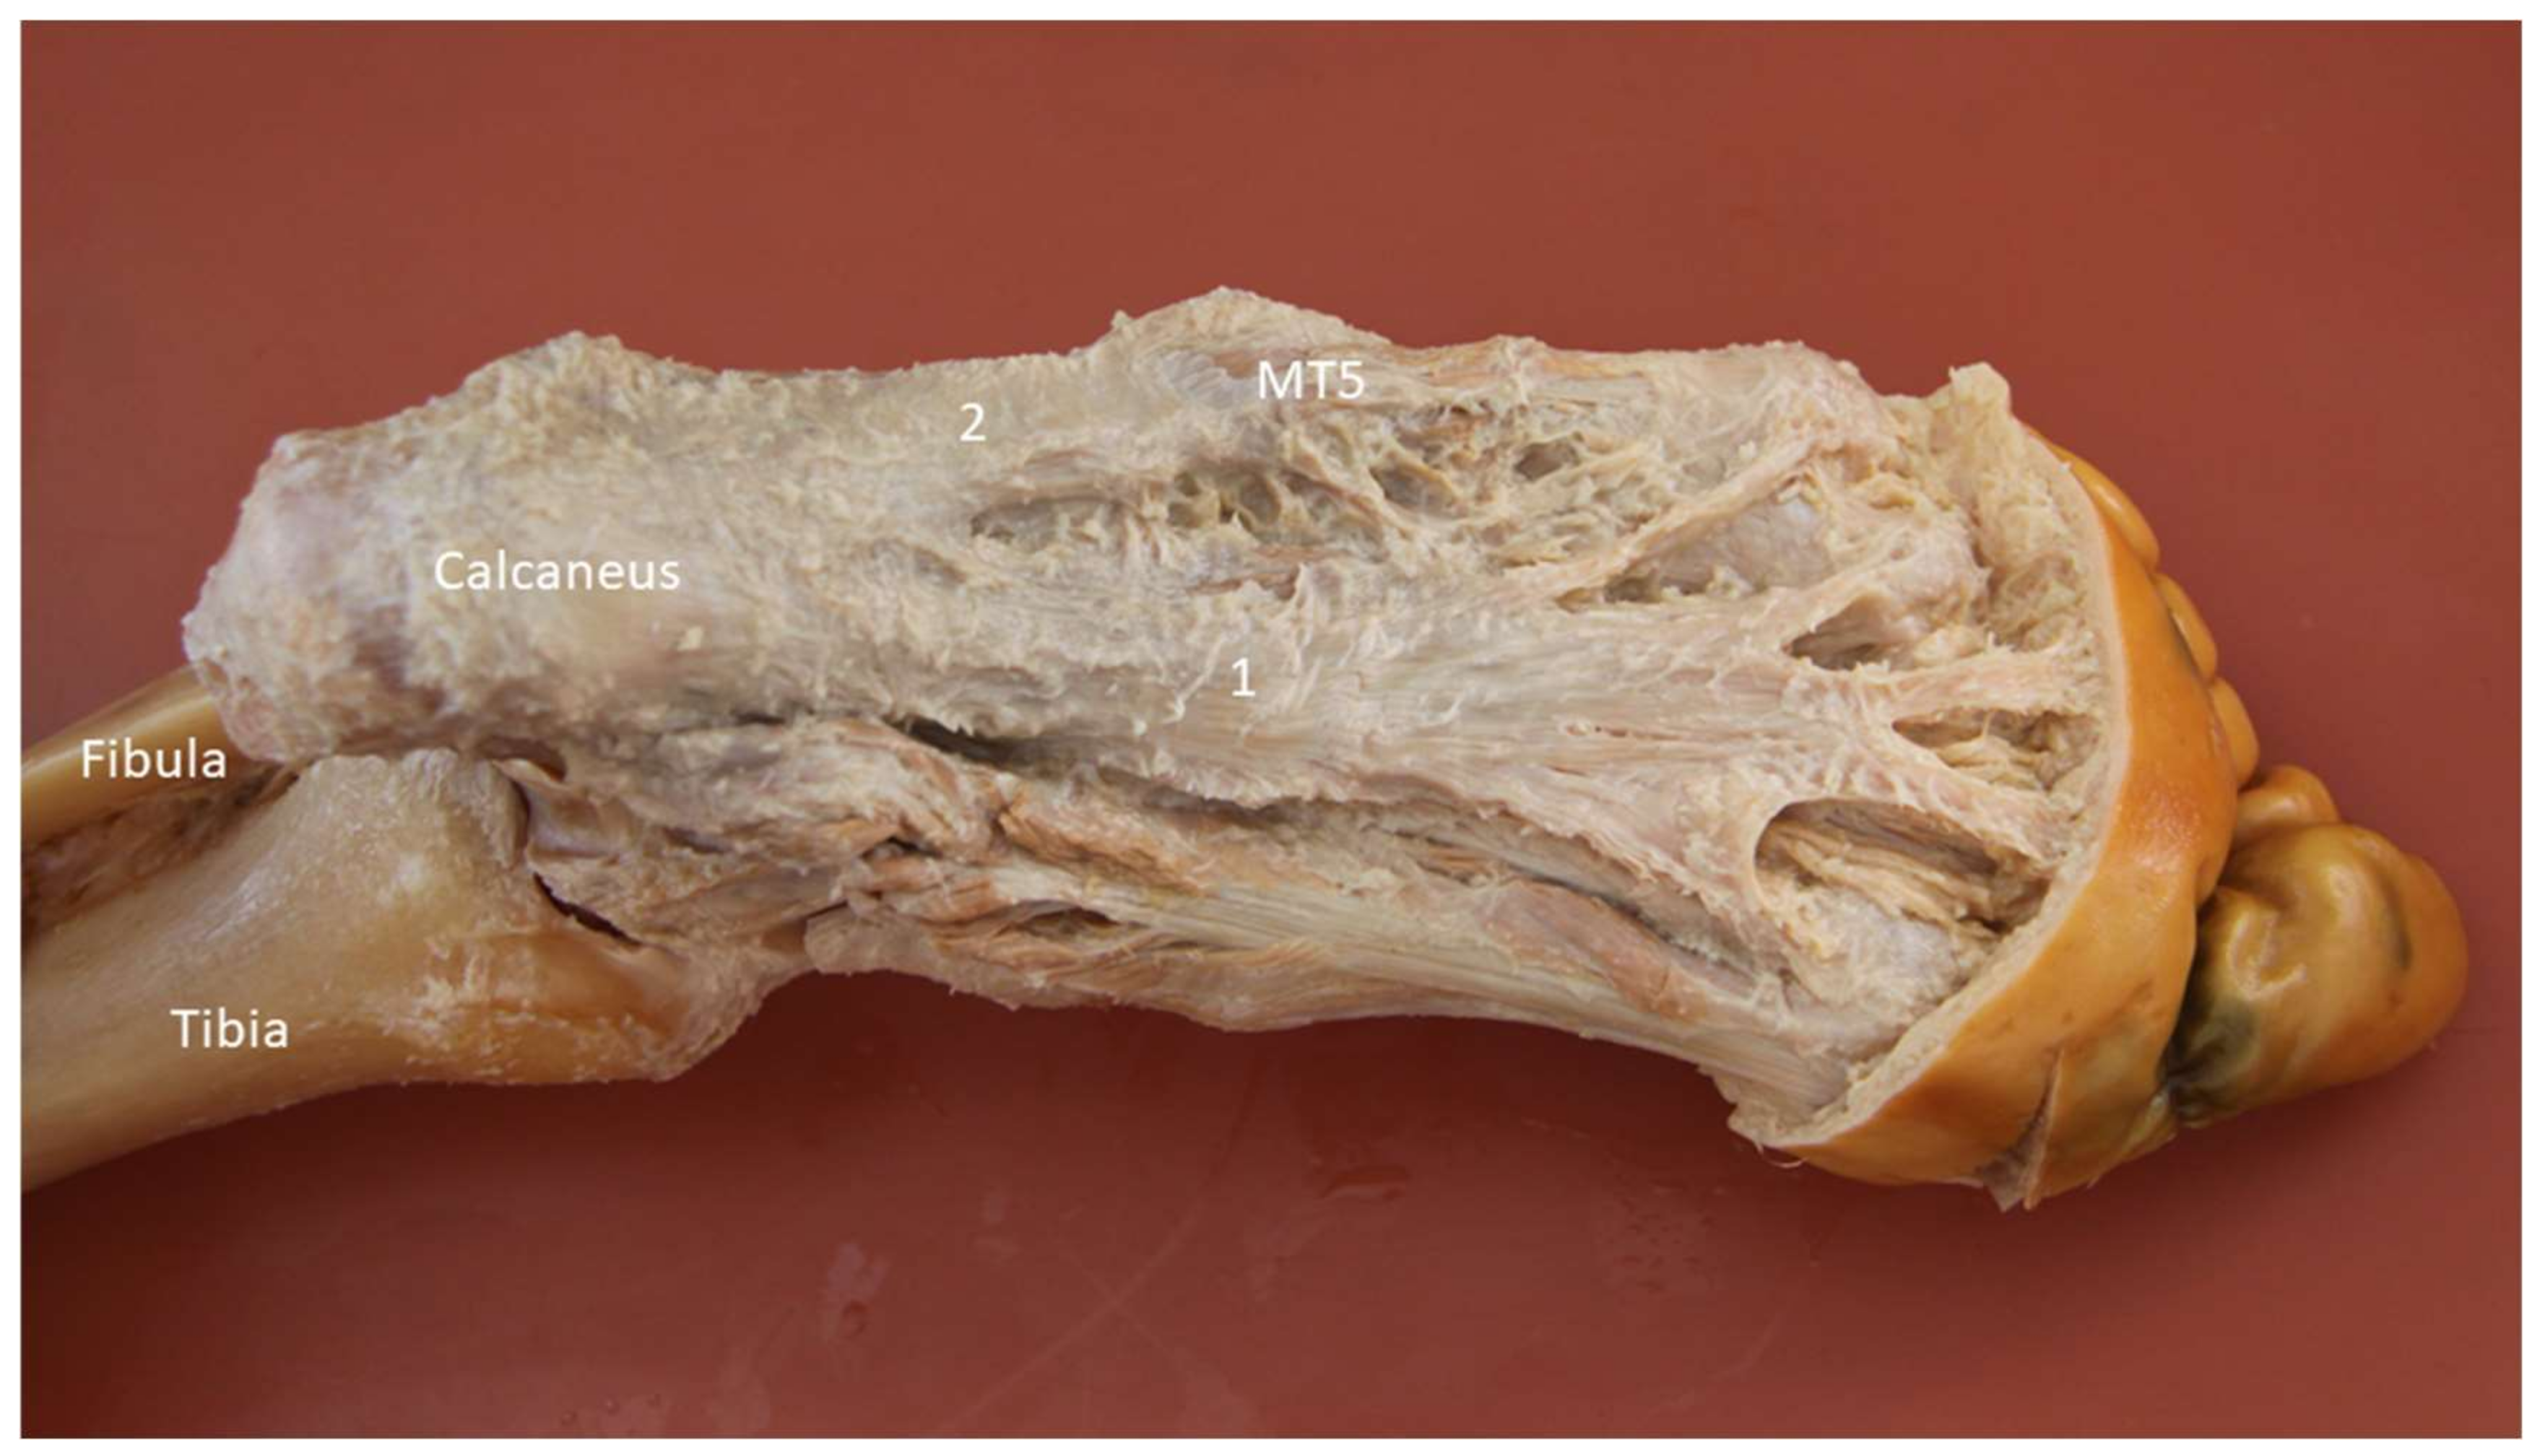

2.11. Lateral Cord of the Plantar Fascia

2.11.1. Anatomy

2.11.2. Scanning Technique

2.11.3. Clinical Relevance